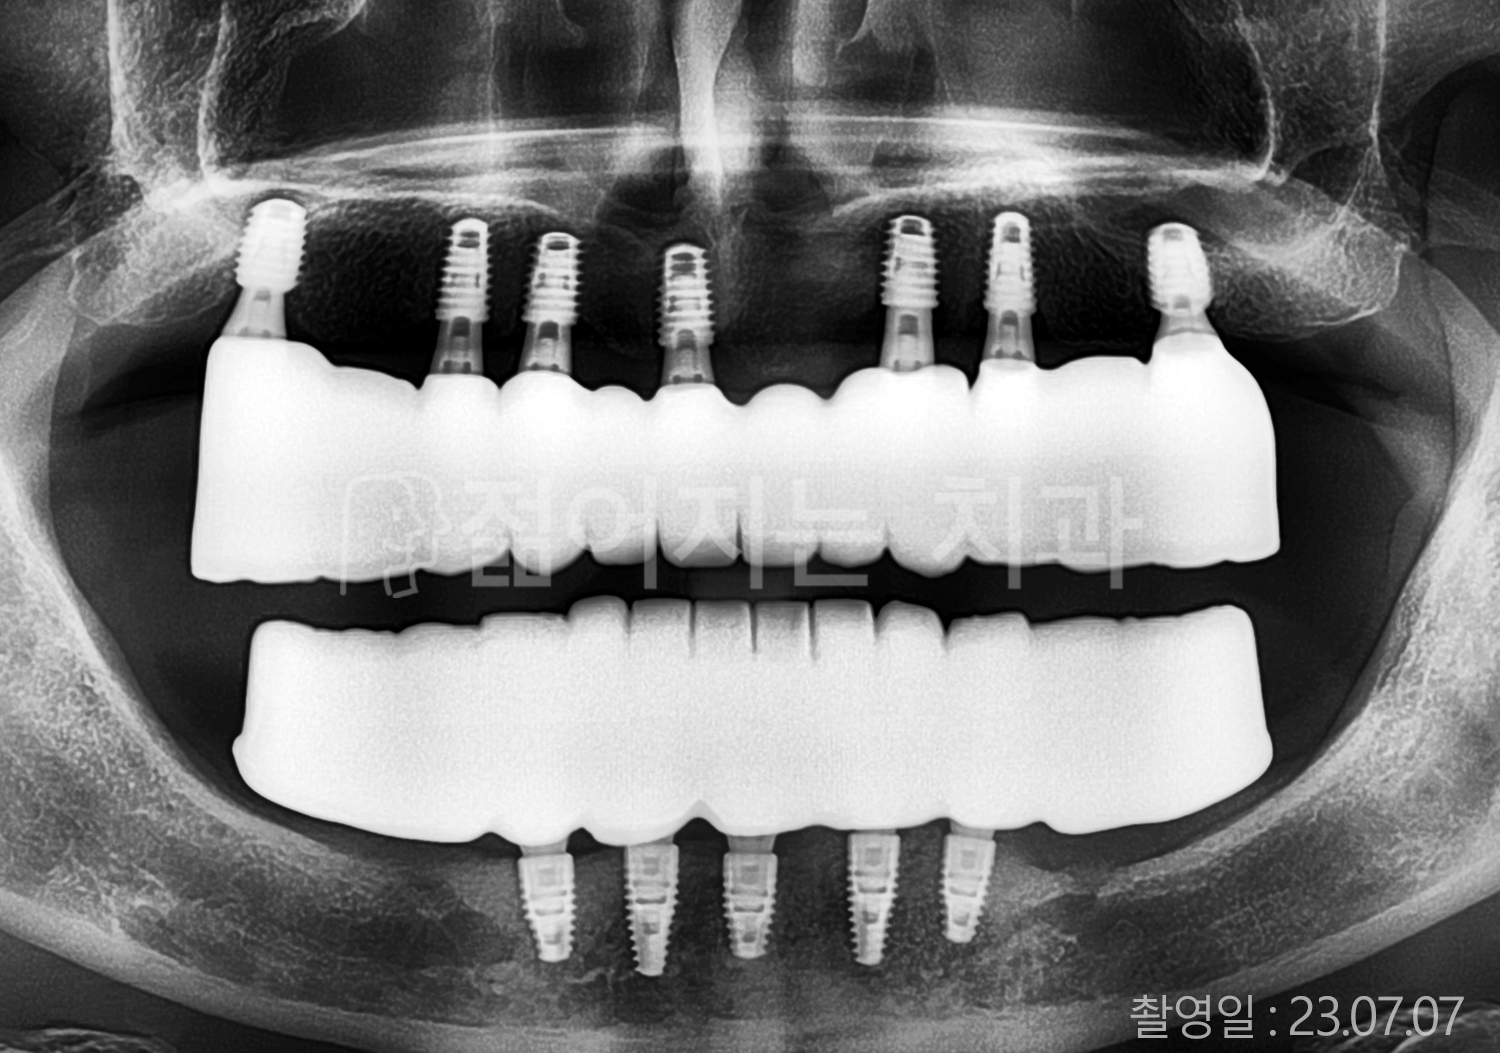

• 40대 전체치아 10개 이상 임플란트

• 70대 당뇨 전체치아 10개 이상 임플란트

• 60대 전체치아 10개 이상 임플란트

• 60대 고혈압, 당뇨, 고지혈증 전체치아 10개 이상 임플란트

• 50대 전체치아 10개 이상 임플란트

• 70대 고혈압, 당뇨 전체치아 10개 이상 임플란트

• 60대 고혈압 전체치아 10개 이상 임플란트

• 50대 고혈압, 당뇨, 고지혈증 전체치아 10개 이상 임플란트

• 60대 고혈압, 고지혈증 전체치아 10개 이상 임플란트